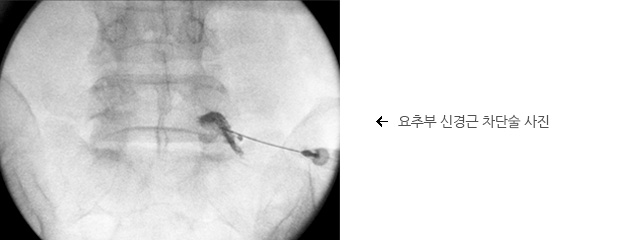

경막외

주사요법 또는

신경근 차단술

심한 다리 통증이 있을 때 사용될 수 있습니다. 이것은 강력한 소염제인 스테로이드와 국소마취제와 함께 유착방지제를 경막외 공간(척추 신경 주위)이나 신경근 주위에 주입하여 신경근 주변의 염증 반응을 가라앉히고 부종을 해결하며 디스크 탈줄증 주변부의 유착을 방지하는 치료이며 대개 3-5회에 걸쳐 시행됩니다.